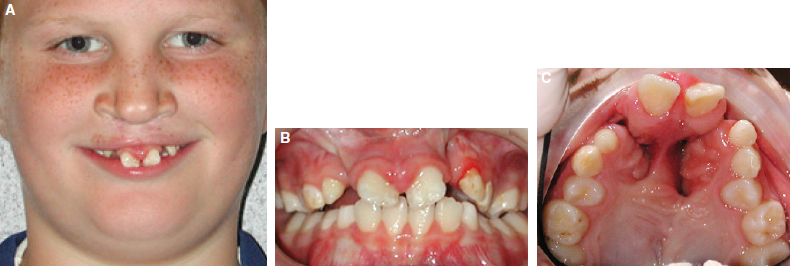

65 ○ The interdisciplinary team approach was developed to provide efficient and effective integrated care for the timing and management of infants born with orofacial clefts and craniofacial anomalies. ○ The orthodontist’s role has traditionally included considerations of both skeletal and dental growth and development. ○ Management of the postnatal growth of the nasomaxillary and mandibular components has been conveniently divided and integrated into four developmental stages: neonatal maxillary orthopedics, the primary dentition, the mixed dentition, and the adolescent and adult permanent dentition. ○ The timing and sequencing of alveolar bone grafts during the mixed dentition stage and orthognathic surgery during the permanent dentition stage require close collaboration of the orthodontist with the surgeon. ○ If skeletal malocclusion is severe in the primary or early mixed dentition, skeletal correction should be delayed until the permanent dentition stage, when a combined approach of comprehensive orthodontics and orthognathic surgery may lead to a more predictable correction. ○ The maxillary incisors adjacent to the cleft site may be tipped, rotated, malformed, or hypoplastic with an absence of bone in the cleft site to support the eruption of the permanent lateral and canine teeth. ○ Orthodontic alignment of maxillary incisors before secondary bone grafting must be limited by the available bone into which the teeth can be moved. ○ In patients with a missing maxillary lateral incisor at the cleft site, the edentulous space can be closed by prosthetic replacement of the lateral tooth (with a fixed partial denture or an endosseus implant) or by orthodontic mesialization of the canine tooth (canine substitution). The document “Parameters for Evaluation and Treatment of Patients with Cleft Lip/Palate or Other Craniofacial Anomalies,” developed by the ACPA in 19921 and later revised in 2009,2 has provided clinicians and third-party payers with guidelines to the scope, timing, and sequencing of treatment for patients with cleft lip or palate. Within the document, the role of the orthodontist is well defined, noting that this role should be a collaborative effort with other dental, medical, and allied health professionals. Emphasis is given to the monitoring of craniofacial growth and development and to providing treatment when necessary to achieve optimal function and appearance. Delivery of orthodontic treatment is recommended in discrete stages of the skeletodental development of the craniofacial complex to prevent continuous treatment from the early mixed dentition to the permanent dentition. These concepts are further explained in texts outlining the role of the orthodontist in the management of cleft lip and palate.3,4 The purpose of this chapter is to discuss the orthodontic principles that govern the contemporary management of patients with an orofacial cleft, from diagnostic considerations to issues of timing and sequencing of treatment. The team approach to the comprehensive care of children born with orofacial clefts requires collaboration among the orthodontist and the other members of the team (Fig. 65-1). The timing and sequencing of orthodontic care requires prioritizing each patient’s other health care needs in the context of an integrated treatment plan derived from a consensus of all team members. Orthodontic interventions may be conveniently divided into four distinct periods defined by age and dental development: neonatal period, primary dentition, mixed dentition, and permanent dentition. Neonatal (or infant) orthopedics occurs during the early postnatal period, usually in the first few months after birth, unless contraindicated by other medical conditions. This intervention was introduced in the 1960s by Burston5 and McNeil6 with the intention that early alignment of the maxillary segments would subsequently allow the dentition to erupt into a more normal occlusion and eliminate the need for orthodontic correction. As this intervention gained popularity, the complexity of the appliances used increased, with both intraoral and extraoral components. The least invasive technique was simple extraoral lip taping (Fig. 65-2). Fig. 65-2 An infant with a complete unilateral left cleft lip and palate. A, Defect before orthopedic intervention. B, Presurgical orthopedics with lip taping to approximate the segments. C, Postsurgical result of definitive lip repair NAM involves an intraoral molding plate, nasal stents, and extraoral taping.7,8 Intraorally, the alveolar ridges are molded to reduce the width of the cleft, achieving approximation of the segments to within 1 to 2 mm of each other. Extraorally, the simultaneous use of nasal stents and taping allows for lengthening of the columella and reshaping of the lower lateral alar cartilages in both bilateral and unilateral clefts. This orthopedic treatment prepares the infant for a one-stage primary lip-nose repair in combination with a gingivoperiosteoplasty to close the alveolar defect. The lengthening of the columella that is achieved from NAM may eliminate or reduce future surgical procedures for columellar lengthening. Because these clinical interventions are performed early in the neonatal period, longitudinal follow-up into adolescence is necessary to evaluate the long-term effects of these early interventions on subsequent nasomaxillary growth. Inspired by the Eurocleft retrospective intercenter project of the 1990s and with advances in clinical outcomes trial methodology, the Dutch intercenter prospective two-arm randomized clinical trial (RCT), also known as Dutchcleft, was designed to study the outcome of neonatal maxillary orthopedics in subjects with unilateral cleft lip and palate (UCLP).9,10 Infant orthopedics in this trial consisted of the use of passive intraoral plates that were adjusted every 3 weeks to guide the maxillary segments and that were replaced with new plates as primary teeth emerged. In a 2005 study by Prahl et al,11 no significant difference could be found between the two randomized groups of infants up to 2 years of age with respect to feeding, nutritional status, or somatic growth. When assessing speech development at age 2.5 years, Konst et al12 found a significant improvement in children treated with infant orthopedics compared with children who did not receive infant orthopedics, with acceptable cost-effectiveness of the orthopedic treatment in regards to speech development. Further reports from the RCT indicated that infant orthopedics had no significant effect on various measures of maxillary arch dimension at ages 4 and 6 years when compared with similarly aged children who had not been treated with infant orthopedics.13 Similar findings were reported with respect to dental arch relationships at ages 4 and 6 years, including overjet, overbite, and sagittal occlusion.14 Cephalometric analyses of soft tissue, skeletal, and dental structures revealed only minor differences at age 6 years between the group treated with infant orthopedics and the untreated group.15 Facial appearance was also evaluated longitudinally in the two groups. Any group differences in facial appearance observed at age 4 years were no longer observed at age 6 years, at which time the better ratings in the infant orthopedic group could only be detected by professional raters.16 The Dutchcleft trial continues to monitor the patients longitudinally into their adolescence. In their conclusions, the investigators warned that clinicians who promote different methods of infant orthopedics, including NAM, should evaluate the long-term effects of their interventions using the rigorous methodology of an RCT.15 In their systematic review of the long-term effects of presurgical infant orthopedics, Uzel and Alparslan17 analyzed eight RCTs and four controlled clinical trials (CCTs), with follow-up periods of up to 6 years. Their results indicate that infant orthopedics has no positive effect on the treatment outcomes evaluated until the age of 6 years, including maternal satisfaction, feeding, speech, facial growth, maxillary arch dimension, occlusion, and nasolabial appearance. If neonatal orthopedics is recommended and feasible, it should be completed in the first few months of life so that definitive surgical lip repair can be achieved within the first 6 months. Palate repair is usually delayed until later in the first year of life. An ongoing controversy relates to the balance between the advantages of restoring the anatomy of the palate in the prelinguistic period and the effects of surgical scar tissue constraining the growth and development of the nasomaxillary complex. Ross18 evaluated the outcomes of both active and passive appliances in children with UCLP at age 10 years after neonatal presurgical infant orthopedics. The results in these groups were compared with those of untreated subjects at matched ages. This cephalometric study of facial growth in treated and untreated children with UCLP reported no beneficial long-term effect of neonatal orthopedics, although some negative effects were observed in those children who had received extraoral taping. As part of the Americleft intercenter study, Daskalogiannakis et al19 found that children with UCLP who were cared for at the only treatment center among the four participating North American treatment centers that did not employ any kind of infant presurgical orthopedics as part of their primary management protocol had the largest mean maxillary prominence (SNA angle) and maxillomandibular convexity (ANB angle) during the mixed dentition stage. None of the centers that provided infant orthopedics used NAM as their presurgical approach, but rather relied on extraoral taping with or without intraoral plates. Clearly, case-controlled studies are needed to establish the long-term effect of infant presurgical orthopedics on various outcomes including growth, dentoskeletal relationships, aesthetics, and socioemotional measures, among others. The primary dentition has usually fully erupted by the time the child is 2.5 to 3 years of age. At this age, the facial soft tissues may mask an underlying skeletal deficiency (Figs. 65-3 and Figs. 65-4). As the toddler grows into a young child, growth of the nasomaxillary complex lags behind that of the mandible, resulting in increasing midfacial deficiency. This may be reflected in the dentition as anterior or posterior crossbites. Patients with bilateral cleft lip and palate (BCLP) may have severe constriction of the posterior segments and protrusion or extrusion of the premaxillary segment (Fig. 65-5). The unilateral or bilateral crossbite may be associated with a functional mandibular shift, which is an early indicator for orthodontic treatment in the primary dentition. However, because the crossbite is likely to recur with the eruption of the permanent successors, a decision may be made to postpone orthodontic intervention until the mixed dentition. Fig. 65-3 A, A 6-year-old girl with repaired complete bilateral cleft lip and palate. B, Her mildly prominent maxilla. C, The primary dentition. D, The bilateral crossbite. E, A palatal fistula and primary laterals that erupted ectopically behind the premaxilla. Fig. 65-4 A, A 7-year-old boy with repaired complete unilateral left cleft lip and palate. B, His mild bimaxillary retrusion. C, The early mixed dentition period. Fig. 65-5 A 5-year-old boy with repaired complete bilateral cleft lip and palate. A, The severe extrusion of his premaxillary segment. B, The premaxillary segment out of the vertical plane of occlusion. C, The severe constriction of the posterior segments and extrusion of the premaxillary segment. Labial and palatal oronasal fistulas are present. Constriction of the dental arch is manifested in both the transverse and sagittal dimensions of the maxilla. Early skeletal midfacial deficiency has been addressed with some success if treated in the primary or early mixed dentition by a protraction face mask (Fig. 65-6). More recently, several studies have reported on the use of miniscrews, or temporary anchorage devices, to support the mandibular dentition while intermaxillary elastics are used to orthopedically protract the maxilla.20,21 Although the occlusal correction includes dentoalveolar proclination of the incisors, the modification and redirection of the skeletal mid-facial deficiency may be transitory. Continued growth restriction of the nasomaxillary complex results in failure to keep pace with normal mandibular growth. Consequently, malocclusion is often reestablished during the late mixed dentition and into the adolescent permanent dentition. Long-term follow up reveals biologic variability in response to the protraction facemask.22 The most logical time for the intervention is when the patient is younger than 10 years of age, during which time the circummaxillary sutures are more responsive. However, a severe malocclusion in the primary or early mixed dentition is unlikely to be corrected with growth modification, which may be a costly and unnecessary burden to the patient and result in questionable and often transient benefit. In such severe malocclusions, skeletal correction should be delayed until the permanent dentition stage, at which time comprehensive orthodontics in combination with orthognathic surgery or maxillary distraction may be more predictably reliable options. Fig. 65-6 An 8-year-old boy with repaired complete unilateral right cleft lip and palate with sagittal and transverse maxillary deficiency. A, The lateral radiograph showed 7 mm reverse overjet. B, Protraction facemask with elastics attached to palatal hooks on expander. C, Palatal expander with bands cemented on the maxillary second primary molars and canines, with palatal hooks to attach elastics. D, Lateral and anterior crossbites improved with palatal expansion and maxillary and dental protraction. E, Facial profile after 9 months of protraction facemask therapy and palatal expansion. F, Correction of anterior and posterior crossbite; the maxillary retainer is in place. G, Superimposition of initial and postprotraction lateral cephalogram tracings shows correction of reverse overjet by incisor proclination and mild maxillary advancement. (Black lines, initial profile at age 8 years; red lines, after 9 months of protraction facemask therapy.) Transition in the child’s dental development occurs between 6 and 12 years of age, as the primary dentition exfoliates and the permanent teeth erupt. Midfacial deficiency at this phase makes the mandible appear prognathic, thus resulting in a concave facial profile (Fig. 65-7). Eruption of the permanent teeth coincides with a period of psychosocial transition during preadolescence when the degree of friendship intimacy intensifies and independence from parents increases.23 Ward et al24 reported that the presence of an orofacial cleft decreases the oral health–related quality of life (OHRQoL) in children and adolescents. In preadolescents with craniofacial anomalies, dissatisfaction with appearance is related to social withdrawal, social anxiety, and self-consciousness.25 This is also the period during which the greatest advances have been made in restoring the bone in the cleft site through the use of secondary alveolar bone grafts, which improve the periodontal support of teeth adjacent to the cleft site and thus reduce or eliminate the need for extraction and prosthetic replacement of compromised teeth. The orofacial cleft disrupts the dental lamina in the cleft site so that the developing permanent teeth may be missing, malformed, or supernumerary. The incisors adjacent to the cleft site may be misplaced, rotated, malformed, or hypoplastic with an absence of necessary bone in the cleft site to support eruption of the permanent lateral incisor and canine (Fig. 65-8). Alveolar bone grafting restores the continuity of the alveolar ridge and allows for closure of oronasal fistulas. Transverse maxillary constriction may be the consequence of scar tissue formation after surgical repair of the secondary palate, resulting in a characteristic omega- or V-shaped arch form, reflected in anterior and posterior dental crossbites (Fig. 65-9). A maxillary expansion appliance is often recommended when the first permanent molars and incisors erupt. Collaboration between the surgeon and the orthodontist in the mixed dentition stage to coordinate the treatment sequence assists in achieving a successful alveolar bone graft with healthy adjacent teeth. Fig. 65-7 A, Same patient as in Fig. 65-4 at 9 years of age. B, The patient had a mild midface deficiency. C, An anterior crossbite was evident during this mixed dentition period. Fig. 65-9 A, The same patient as in Figs. 65-4 and 65-7, shown at age 9 years, with bilateral posterior and anterior crossbites. Note the severely rotated maxillary central incisor next to the cleft. B, The V-shaped arch form and palatal scarring. Primary alveolar bone grafting typically involves the placement of a bone graft in the neonatal cleft site at the time of primary surgical lip repair and hence before eruption of the primary incisors. Data suggests that this method may be deleterious to maxillary growth, so most cleft palate teams prefer to defer bone grafting until further maxillary growth and development has occurred.26 Secondary, or delayed, alveolar bone grafting is performed after primary lip repair and is classified according to the age at which the bone graft is placed: early secondary bone grafting (2 to 5 years), intermediate secondary bone grafting (6 to 15 years), or late secondary bone grafting (adolescence to adulthood). The principles of secondary bone grafting were first introduced by Boyne and Sands.27,28 In 1986, Bergland et al29 studied 378 consecutive patients who had undergone secondary alveolar bone grafting, showing that the best outcomes were achieved in patients in whom the bone graft was performed before the eruption of the maxillary canine. This report was followed by a cephalometric study that compared maxillary growth in children who received secondary alveolar bone grafting between the ages of 8 and 12 years with the maxillary growth in children who did not have a bone graft.30 There was no adverse effect of bone grafting on anteroposterior or vertical maxillary growth, a finding attributed to the postponement of grafting until most of the growth of the anterior maxilla had occurred and to the ability of the grafted bone to develop vertically with the alveolus.30 Since the publication of these landmark articles, current opinion supports the intermediate period as the most appropriate time for grafting. This practice has the greatest benefits and least risk for interfering with midfacial and skeletodental growth and development. Levitt et al31 demonstrated that there were no significant differences in maxillary sagittal or vertical growth after secondary bone grafting in patients with complete UCLP when compared with that in patients with similar clefts who did not receive a bone graft. The multicenter Eurocleft study of treatment outcomes in patients with complete cleft lip and palate compared craniofacial form in individuals treated at five European centers.32 The only center performing primary bone grafting obtained less favorable results in vertical maxillary growth, soft tissue sagittal relationships, and soft tissue facial proportions than the centers that performed secondary bone grafting between the ages of 8 and 11 years. Moreover, the center that used primary bone grafting obtained the least favorable dental arch relationships, with almost 50% of the patients needing surgical correction of maxillary retrusion at 17 years of age.33 In Americleft, the North American intercenter study of treatment outcomes in patients with complete UCLP, the only center performing primary bone grafting obtained the least favorable dental arch relationships, lowest maxillary prominence, and least favorable maxillomandibular relationships.19,34 Further justification for performing alveolar bone graft surgery during the mixed dentition period is that patients at this age are usually cooperative with the orthodontic procedures, such as maxillary expansion, that may be indicated before grafting.35 The donor site for graft harvest, typically the anterior iliac crest, has an acceptable volume of bone for successful grafting at this age.35 A survey of alveolar bone grafting practices among ACPA teams across North America revealed a consensus for the type of alveolar bone grafting performed: most of the centers perform intermediate secondary alveolar bone grafting.26 Therefore the following discussion focuses on alveolar bone grafting during this time period. A bone graft placed before eruption of the teeth adjacent to the cleft (especially the lateral incisor or canine when located on the posterior segment) provides a bony matrix to enable the eruption of these teeth into a continuous alveolar ridge, generating additional alveolar bone in the area29 (Fig. 65-10). Generally, grafting is done before the eruption of the permanent maxillary canine on the cleft side, which is usually located in the alveolar segment posterior to the cleft. Teeth directly adjacent to the cleft, particularly maxillary central or lateral incisors located on the proximal (mesial) segment, often erupt into unfavorable positions and may be ectopic, be rotated, or have an unfavorable axial inclination. This malposition is usually a reflection of the anatomy of the alveolar cleft, which is usually narrower at the alveolar margin and wider at the piriform aperture, thus limiting the amount of bony support for the teeth, especially along the root surface directly facing the cleft. Radiographs of these teeth often demonstrate a thin layer of cortical bone along their distal surface (see Fig. 65-10), bone that may be at risk for resorption if nonjudicious presurgical orthodontic uprighting is carried out. If a bone graft is placed before extensive orthodontic alignment of erupted teeth adjacent to the cleft, crestal bone heights are preserved, and postsurgical orthodontic alignment can be accomplished with minimal risk of bone resorption while ensuring adequate bony coverage of the roots. Oronasal fistulas can allow for nasal air escape with speech and may contribute to velopharyngeal dysfunction in patients with cleft lip and palate.36 A three-layered closure technique, with the graft interposed between the two soft tissue layers, yields a high success rate of fistula closure. Surgical closure of oronasal fistulas with secondary alveolar bone grafting often results in a significant improvement in speech, manifested as decreased nasality and nasal emission.37 Occasionally, large palatal fistulas cannot be closed at the time of alveolar bone grafting without compromising the integrity of the graft. On a case-by-case basis, surgeons may elect to close the palatal fistula in a separate surgical procedure, usually before alveolar bone grafting. Fig. 65-10 A, A bone defect at the cleft site in a 10-year-old patient before alveolar bone grafting. More than two thirds of the roots of the transposed lateral incisor and canine have developed (close to eruption). Note the thin layer of bone covering the adjacent central incisor. No orthodontic incisor alignment is planned. B, Periapical radiograph taken 4 months after alveolar bone grafting, showing excellent fill of the cleft defect with cancellous bone. The canine is erupting through the grafted bone. Alveolar bone grafting contributes to improved nasal and lip symmetry and provides a stable platform on which the nasal structures are supported.38 If performed alone or in combination with tip rhinoplasty (often as a separate procedure) alveolar bone grafting often yields aesthetic benefits. After a successful bone graft, the orthodontist can move the teeth bodily and upright roots into the cleft site without risk of compromising their periodontal support.29,39 The prosthodontist also can achieve a more aesthetic and hygienic prosthesis to replace missing teeth in the cleft area.39 Insertion of endosseous implants into the grafted cleft is possible and provides functional stimulation to the transplanted bone.40 Patients with bilateral clefts present with varying degrees of mobility of the premaxilla, which usually remains unstable throughout life.29 In such cases, secondary alveolar bone grafting stabilizes the premaxilla, allowing patients to have functional incisors with adequate stability to serve as abutments for fixed prostheses.29,39 The optimal time for performing secondary alveolar bone grafting can be established according to the age of the patient or, alternatively, according to dental development as defined by stage of root development. Chronologic Age By definition, secondary bone grafting is done during the mixed dentition stage, before the eruption of the maxillary canine (or lateral incisor, if located in the alveolar segment posterior to the cleft). Once teeth have erupted into the cleft site, their limited periodontal support will not improve with a graft, because the transplanted bone will not adhere to the tooth surface.35 The height of the crest of alveolar bone eventually resorbs to its original level. It is therefore essential to perform the graft before the eruption of the permanent teeth adjacent to the cleft. This period may encompass a range of several years, from age 6 to 15 years, when grafting has a high success rate. However, evidence shows that the older the patient is at the time of surgery, the poorer the outcomes of secondary bone grafting.41 Therefore the available evidence supports an optimum age at which patients should receive bone grafts. Using chronologic age alone for defining the optimal age for grafting may not be clinically valid, because patients with cleft lip or palate have delayed development of the teeth compared with individuals without clefts.42 Moreover, teeth adjacent to the cleft side demonstrate more developmental delay than the contralateral teeth.42 Dental development, based on assessment of the number of permanent teeth erupted and the extent of root formation, represents a more accurate indicator of the optimal timing for the bone grafting procedure than does chronologic age alone. Maxillary Canine Development One developmental indicator that has been proposed for establishing the optimal timing for grafting is the root formation of the permanent maxillary canine on the cleft side. It has been recommended that the optimal timing for secondary grafting is when the maxillary canine has developed one half to two thirds of its final length, which generally occurs between the ages of 8 and 11 years39,43 (see Fig. 65-10). This is advocated because when the root has developed two thirds of its expected full length, accelerated eruption of the canine occurs, and it can then erupt spontaneously through the graft, bringing additional alveolar bone into the area. In a retrospective study of patients with non-syndromic UCLP, Mercado et al44 demonstrated a significant positive correlation between stage of canine root development at the time of surgery and the outcome of bone grafting. Maxillary Lateral Incisor Development A study of patients with UCLP demonstrated that the cleft-side permanent lateral incisor was present in 50.2% of patients.45 Of these patients, 76.5% had the permanent lateral incisor located on the posterior segment, distal to the cleft. When the maxillary lateral incisor is located in the posterior segment, alveolar bone adjacent to the cleft is generally insufficient to support the lateral incisor as it drifts anteriorly and occlusally along its eruptive path into the arch. In such cases, grafting before the eruption of the lateral incisor may be advisable to improve the prognosis of this tooth.46,47 The developmental indicator of one half to two thirds of canine root formation for timing of an alveolar bone graft may be too late when the aim is to preserve an existing lateral incisor. Lilja et al48 discourage the use of root formation as an indicator for graft placement, proposing the assessment of the thickness of bone covering the crown (of the lateral incisor or canine) to determine timing of bone grafting. They advocate that bone grafting be performed when there is a thin layer of bone covering the tooth distal to the cleft. Other studies have reported no significant relationship between the degree of radiographic canine eruption through the alveolar cleft and the outcome of secondary bone grafting.49,50 The sequencing of procedures associated with placement of an alveolar bone graft requires interdisciplinary communication and cooperation for a successful outcome. Orthodontists, general or pediatric dentists, oral surgeons, and plastic surgeons intervene in a coordinated fashion to ensure that one discipline’s efforts do not interfere, delay, or jeopardize those of the other disciplines. Parents and caregivers may be concerned about teeth (often supernumerary) that have erupted near the cleft, either palatally or high in the labial vestibule. Ectopic teeth present a challenge for the parents and patient to maintain good hygiene because of their location and limited accessibility. The role of the general or pediatric dentist is to ensure that the patient and parents are aware of the ectopic teeth and that they are instructed on good oral hygiene practices to maintain the teeth free of decay, out of traumatic occlusion, and not contributing to traumatic ulcerations of the surrounding mucosa. The preservation of these teeth before surgery maintains the supporting alveolus. The general or pediatric dentist should restore any decayed teeth adjacent to the cleft before the grafting procedure. On the other hand, erupted teeth adjacent to the cleft that have poor periodontal or restorative prognosis should be extracted at least 2 months before surgery to allow the soft tissues to heal (see Fig. 65-8). This will allow healthy mucosal flaps to be reflected, positioned, and sutured over the grafted bone at the time of surgery. Healthy ectopic primary or supernumerary teeth that have erupted along the line of the cleft should also be removed at least 2 months before surgery to allow access to the surgical site. Orthodontic treatment may be required presurgically to reposition maxillary teeth that are in traumatic occlusion or to expand a severely constricted maxilla, thus providing the surgeon better access to the cleft defect. In bilateral cases, a mobile premaxilla with anterior traumatic occlusion may need to be addressed with a posterior bite plane to minimize mobility, which may compromise the success of the grafts during the healing period.35 A severely extruded premaxilla may need to be intruded to level it with the posterior segments (Fig. 65-11). This can be done with an active intrusion arch ligated over a passive segmental wire to the maxillary incisors. Alternatively, miniscrews placed directly on the premaxilla may serve as a point of attachment during intrusion, repositioning, and stabilization of the premaxilla.20 Other surgical procedures such as minor aesthetic revisions of the nose and lip, as well as the insertion of tympanostomy tubes, may be undertaken during the same general anesthesia setting of the alveolar bone graft. Dental prophylaxis and restorative work are generally not performed in conjunction with the bone grafting procedure to minimize the release of bacteria and debris into the surgical site. Unerupted teeth with poor prognosis adjacent to the cleft can be removed by the surgeon intraoperatively once the mucosal flaps have been reflected.